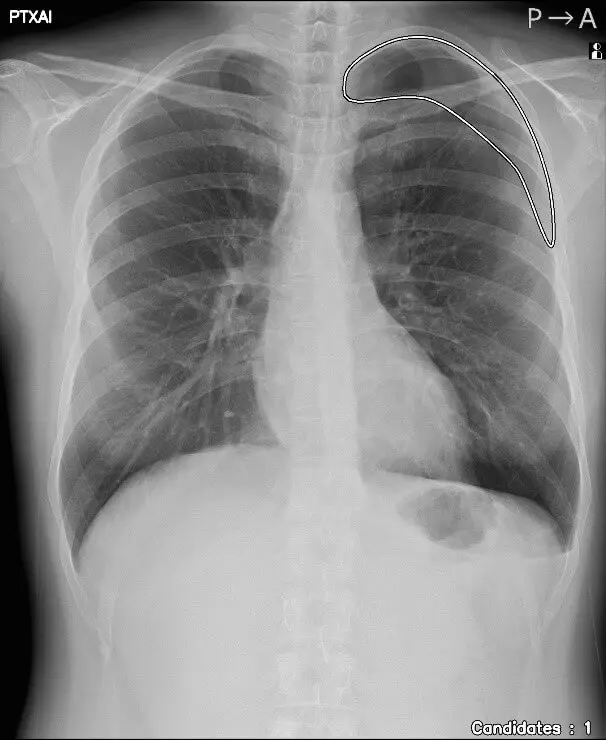

気胸の診断支援を行うプログラム「CXR Finding-i 気胸検出タイプ」と連携することで、ガイドラインにおいて一般撮影で診療放射線技師が発見した場合に報告すべきSTAT画像所見の一つに挙げられている気胸の候補を高精度で検出することができます。

「CXR Finding-i 気胸検出タイプ」により解析された気胸の検出領域を表示

「CXR Finding-i 気胸検出タイプ」は、胸部単純X線画像をAI※2で解析することで重要所見である気胸の候補を迅速に検出し、候補領域を画像上に表示することで見落とし防止を支援します。病変検出性能を示す指標である感度※3は95%と高い水準を実現していることに加え、気胸が存在しない画像をAIが正しく陰性(気胸なし)と判断した割合を示す特異度※4は96%であり、病変を見逃さないようにしつつ偽陽性も抑制した高精度の検出性能が特長です。

人のレントゲン写真 オリジナル画像

オリジナル画像

人のレントゲン写真 気胸の検出領域を表示

気胸の検出領域を表示